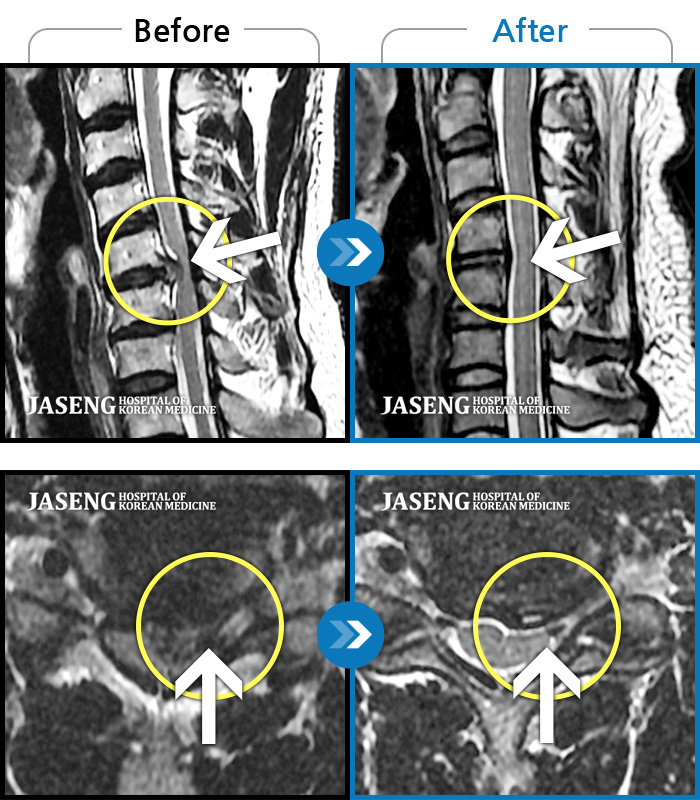

허리디스크

부천 · 최요섭 원장

양측 허리와 골반 통증, 양측 다리 저림

촬영시기

2018.05.17 ~ 2019.10.17

2019.12.13